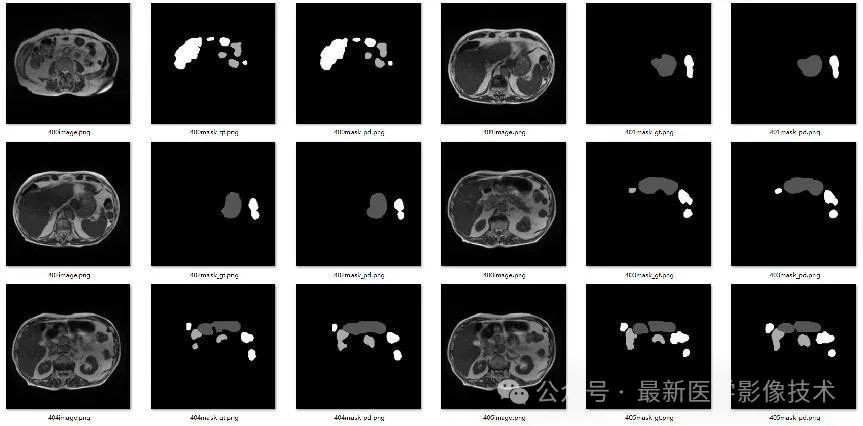

4、验证集部分分割结果